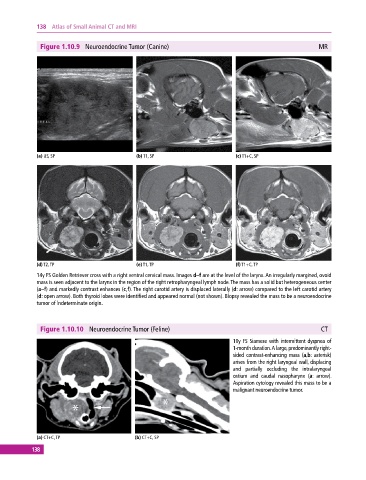

Figure 1.10.9 Neuroendocrine Tumor (Canine) MR

(a) US, SP (b) T1, SP (c) T1+C, SP

(d) T2, TP (e) T1, TP (f) T1+C, TP

14y FS Golden Retriever cross with a right ventral cervical mass. Images d–f are at the level of the larynx. An irregularly margined, ovoid

mass is seen adjacent to the larynx in the region of the right retropharyngeal lymph node. The mass has a solid but heterogeneous center

(a–f) and markedly contrast enhances (c,f). The right carotid artery is displaced laterally (d: arrow) compared to the left carotid artery

(d: open arrow). Both thyroid lobes were identified and appeared normal (not shown). Biopsy revealed the mass to be a neuroendocrine

tumor of indeterminate origin.

Figure 1.10.10 Neuroendocrine Tumor (Feline) CT

10y FS Siamese with intermittent dyspnea of

1‐month duration. A large, predominantly right‐

sided contrast‐enhancing mass (a,b: asterisk)

arises from the right laryngeal wall, displacing

and partially occluding the intralaryngeal

ostium and caudal nasopharynx (a: arrow).

Aspiration cytology revealed this mass to be a

malignant neuroendocrine tumor.

(a) CT+C, TP (b) CT+C, SP